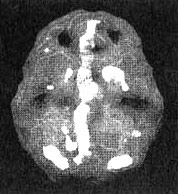

Стивен (39 лет), инженер на радиостанции, поступил в клинику с жалобами на суицидальные мысли. Недавно после восьми лет брака он развелся с женой. За время семейной жизни супруги несколько раз физически оскорбляли друг друга, за что Стивена посадили в тюрьму. Он тоже жаловался на сильную вспыльчивость. За рулем он часто орал на других водителей, а на работе часто приходил в негодование. При поступлении в клинику он был депрессивен и плаксив, жаловался на проблемы со сном и низкую концентрацию. Кроме того, он рассказал, что у него бывают короткие эпизоды замешательства, он приходит в сильнейшую ярость по незначительным поводам, а иногда боковым зрением видит тени. ЭЭГ была нормальной. Сканирование SPECT выявило значительное повышение активности в глубоких тканях левой височной доли и в поясной извилине.

Мозг Стивена. Суицидальные мысли

Трехмерное изображение, вид снизу — активный мозг.

Трехмерное изображение, вид сбоку — активный мозг.

Обратите внимание на выраженно повышенную активность в левой височной доле и в поясной системе (стрелки).